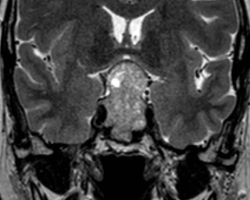

Un homme de 55 ans, n’ayant aucun antécédent personnel est envoyé pour réaliser une IRM par son ORL pour exploration d’acouphènes associés à une hypoacousie droite ainsi que des vertiges et une paralysie faciale périphérique droite d’apparition récente. […]